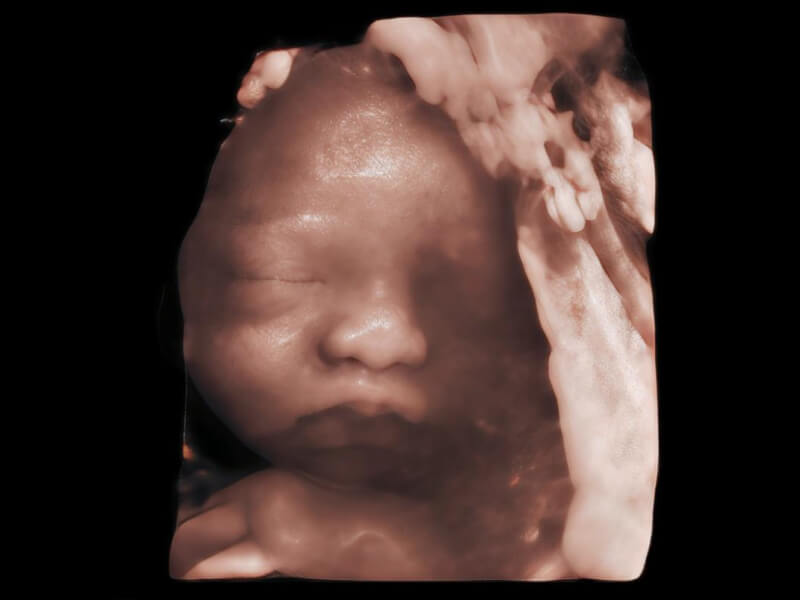

作為開(kāi)立醫(yī)療全新打造的超高端旗艦超聲產(chǎn)品,從探頭抬起喚醒開(kāi)啟掃查到多維探頭發(fā)射接收,通過(guò)先進(jìn)的場(chǎng)成像發(fā)射、自適應(yīng)聚合重建等技術(shù),基于RF Data原始射頻數(shù)據(jù)在圖像生成、高端功能等方面實(shí)現(xiàn)突破,為婦產(chǎn)科、兒科提供全方位臨床解決方案。

夢(mèng)溪?P80以“關(guān)愛(ài)女性”為基石,提供全方位的解決方案,量身定制以滿(mǎn)足女性的健康需求,涵蓋婦科、生殖健康檢查、產(chǎn)前篩查及產(chǎn)后康復(fù)等領(lǐng)域。